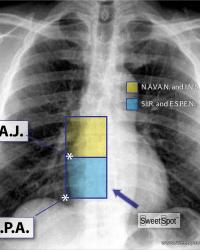

Figure - 03

Dual energy CXR. Another variation in Sweet Spot™ dimensions |